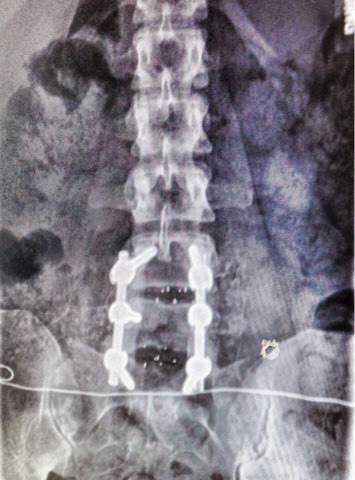

Happy anniversary titanium and donor bone that makes me move! We might not able to dance with pelvic thrusts anymore but we can walk AND we know when we have to tinkle and isn't that what it's all about?